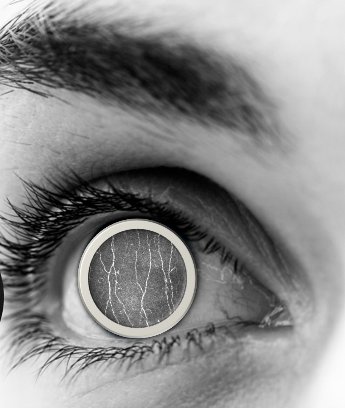

Loss Functions Evaluation for Corneal Nerve Segmentation

Corneal confocal microscopy (CCM) has been advocated as a non-invasive technique for objective diagnosis of very early neuropathy in patients by scanning the corneal subbasal nerve plexus. The obtained images provide a range of research opportunities to be explored. Current research revolves around providing automated solutions for nerve segmentation in CCM images. A common problem in CCM nerve segmentation is that the total number of nerve pixels is much smaller than the total number of background pixels. Thus, accuracy is not a very suitable evaluation metric for this problem. At the same time, the loss function used in the deep learning network influences the performance of the network. It is an important constituent of a deep learning segmentation network. In this project, we address the problem of low sensitivity of nerves in automatic segmentation caused by imbalanced pixel distribution in the CCM images. We evaluate different loss functions for this problem.

A comparison is made between cross entropy, dice loss, and Tversky loss using the most popular CNN for biomedical image segmentation, U-Net.